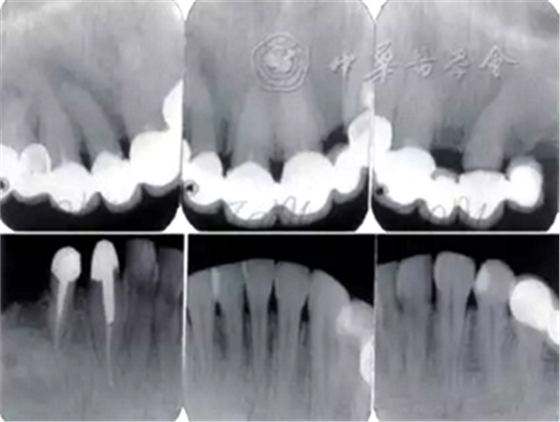

3.影像學檢查:

全口根尖X線片示鄰面骨嵴頂影像模糊;根管欠填、根充不致密,、未見根管治療影像,、根尖周可見低密度影像(圖2)。

圖2 患者初診時全口根尖X線片